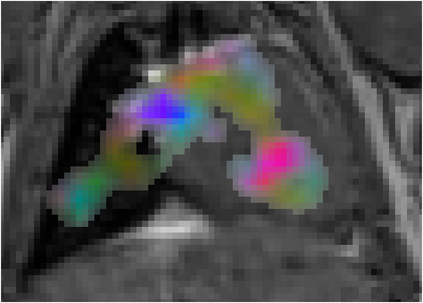

Various imaging modalities allow for time-dependent image reconstructions from measurements where its acquisition also has a time-dependent nature. Magnetic particle imaging (MPI) falls into this class of imaging modalities and it thus also provides a dynamic inverse problem. Without proper consideration of the dynamic behavior, motion artifacts in the reconstruction become an issue. More sophisticated methods need to be developed and applied to the reconstruction of the time-dependent sequences of images. In this context, we investigate the incorporation of motion priors in terms of certain flow-parameter-dependent PDEs in the reconstruction process of time-dependent 3D images in magnetic particle imaging. The present work comprises the method development for a general 3D+time setting for time-dependent linear forward operators, analytical investigation of necessary properties in the MPI forward operator, modeling aspects in dynamic MPI, and extensive numerical experiments on 3D+time imaging including simulated data as well as measurements from a rotation phantom and in-vivo data from a mouse.